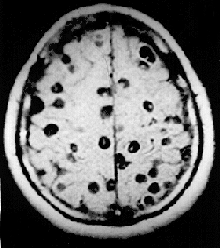

MRI-opname van een patiënt met ernstige hersencysticercose

Lintwormen (Cestoda) en Digenea kunnen vele ziekten veroorzaken bij de mens en bij vee. Veel soorten Monogenea kunnen ook visteelt ernstig aantasten.[15] Schistosomiasis is de op een na dodelijkste parasitaire ziekte in tropische landen, na malaria. Geschat wordt dat wereldwijd ongeveer 200 miljoen mensen besmet zijn met de ziekte, voornamelijk in Afrikaanse landen. Het sterftecijfer van de schistosomiasis is laag, maar manifesteert zich gewoonlijk als chronische ziekte waarbij de ingewanden beschadigd raken. De ziekte wordt veroorzaakt door verschillende soorten van het geslacht Schistosoma: platwormen die door de menselijke huid kunnen dringen.

In het jaar 2000 waren naar schatting 45 miljoen mensen besmet met de runderlintworm (Taenia saginata) en 3 miljoen met de varkenslintworm (Taenia solium).[15] Een infectie van het spijsverteringsstelsel door een volwassen lintwormen veroorzaakt buikklachten die, hoewel onaangenaam, zelden invaliderend of levensbedreigend zijn.[16] Wanneer de larven van T. solium echter het centrale zenuwstelsel binnendringen (cysticercose), is de kans op epilepsie groot. In 2000 waren ongeveer 39 miljoen mensen besmet met trematoden die van nature in vis en schaaldieren parasiteren. Infectie door de vislintworm Diphyllobothrium kan een vitamine B12-tekort en, in ernstige gevallen, megaloblastaire anemie veroorzaken.